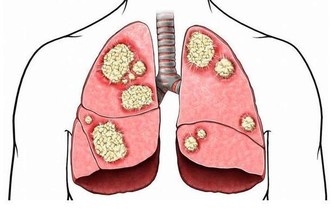

2、腸道堵塞

當腸道出現堵塞的時候,也會出現口臭、口中有異味的的情況!如果,同時伴有便秘、出現色斑、膚色粗糙、晦暗等情況,則要考慮是腸道堵塞問題!